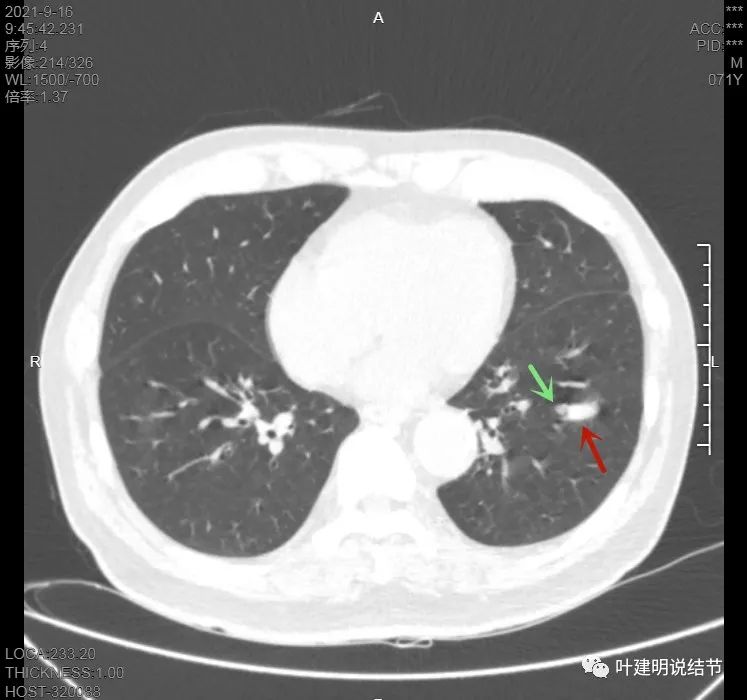

上图见主病灶长方形,边缘平直且光滑,没有毛刺、分叶或胸膜牵拉,粉色箭头示小病灶,在主病灶边上

上图示主病灶边缘非常光滑,膨胀性不明显

上图似乎边缘有点磨玻璃,但这可能是病灶横断面扫到组织相对较少或较薄的地方,其实并不是磨玻璃成分

上图是病灶下缘的样子